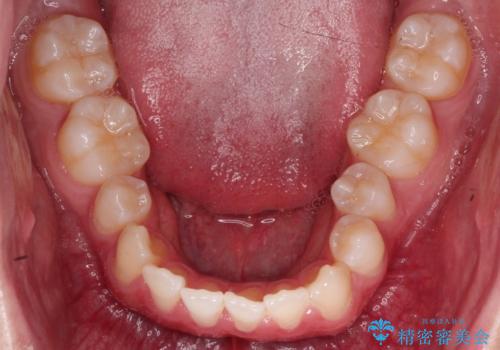

- 前歯のガタガタや正中の不整を改善するために、右上4、左上4、左下4を抜歯し、矯正治療を行いました。この治療により、見た目だけでなく、咬合のバランスも改善され、患者様の口腔内の健康が向上しました。

審美ワイヤー装置は、見た目を重視した矯正治療において非常に有効な選択肢です。患者様のニーズに応じた治療が可能で、美しい歯並びを目指すことができます。